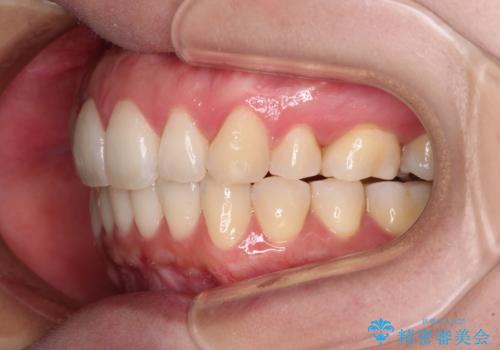

再矯正で突出した口元を引っ込める 抜歯矯正の後戻り

- 抜歯矯正の後戻りで前歯が突出してきていることを気にして来院された患者様です。

口元の突出感を改善するにあたり、抜歯矯正は行うことができないため、奥歯の後方移動とIPR(歯と歯の間を削る)により達成することとしました。

再度後戻りしたときに対応しやすいよう、インビザラインにて矯正治療を行うこととしました。

しっかりと装着時間を守り、ゴムかけにも協力していただいたので、口元を引っ込めることができました。